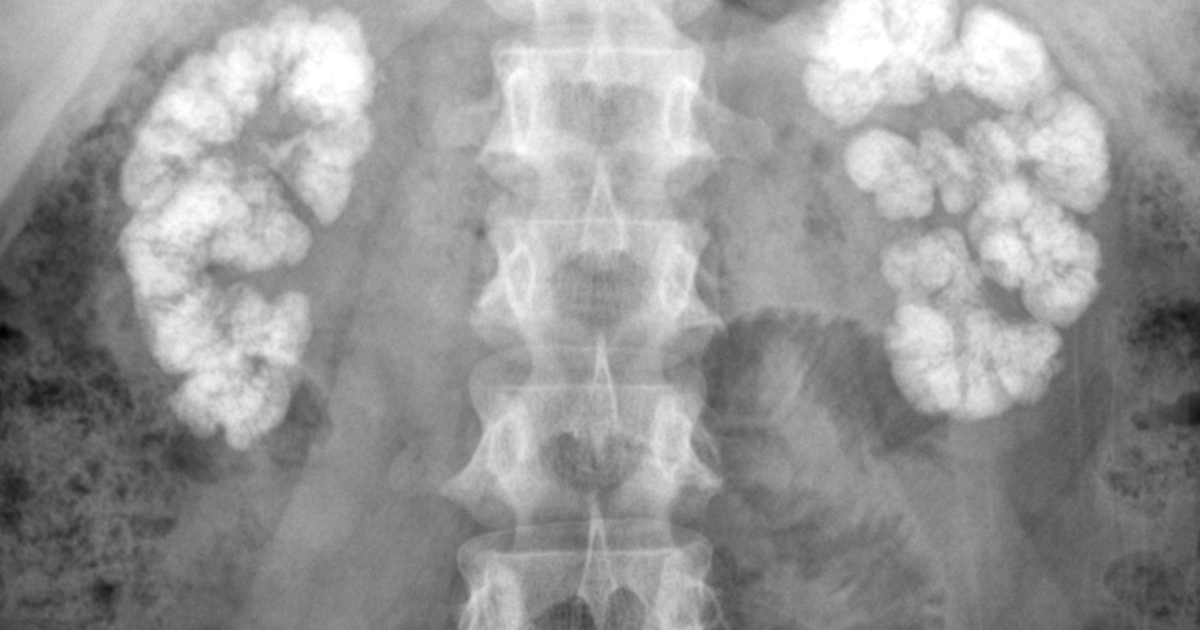

Medullary NephrocalcinosisPlain Film Sumer's Radiology Blog Medullary Sponge Kidney Nephrolithiasis Urolithiasis (ul) is the presence of stones/calculi anywhere within the urinary. patients with medullary sponge kidney and symptomatic nephrolithiasis can be treated with extracorporeal shock wave lithotripsy. Usually it does not cause. may present with flank pain, recurrent urinary tract infections (utis), haematuria (gross and microscopic),. medullary sponge kidney (msk) disease is a rare condition affecting the. Medullary Sponge Kidney Nephrolithiasis.

LearningRadiology Medullary, Nephrocalcinosis, calcification, renal Medullary Sponge Kidney Nephrolithiasis Urolithiasis (ul) is the presence of stones/calculi anywhere within the urinary. medullary nc is by far the most common form. Usually it does not cause. recurrent nephrolithiasis (renal stones) is a major. medullary sponge kidney (msk) is a congenital disorder, meaning it is present at birth. medullary sponge kidney (msk) disease is a rare condition affecting. Medullary Sponge Kidney Nephrolithiasis.